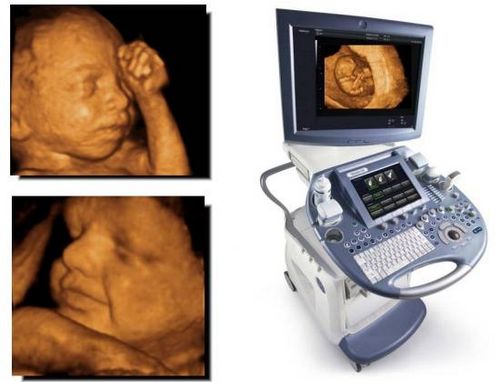

Медицина не стоїть на місці. Зараз будь-яка майбутня мама може подивитися на свою дитину з монітора. Як він виглядає, які у нього риси обличчя, на кого схожий, що зараз робить.

Це дуже популярно серед вагітних жінок. Лікарям такий спосіб обстеження теж зручний. Дозволяє добре розгледіти будова черепа, носогубний трикутник, очні западини, щелепу, розміри кінцівок, пальців. Визначається і стать дитини.

3D буде більш інформативно швидше з 24 тижнів вагітності, коли дитина вже підріс, округлився, став схожий на маленьку людину. За допомогою 3D-УЗД доктору легше визначити стать дитини. Тому, обстеження 3D-УЗД на ранньому терміні буде швидше марним.